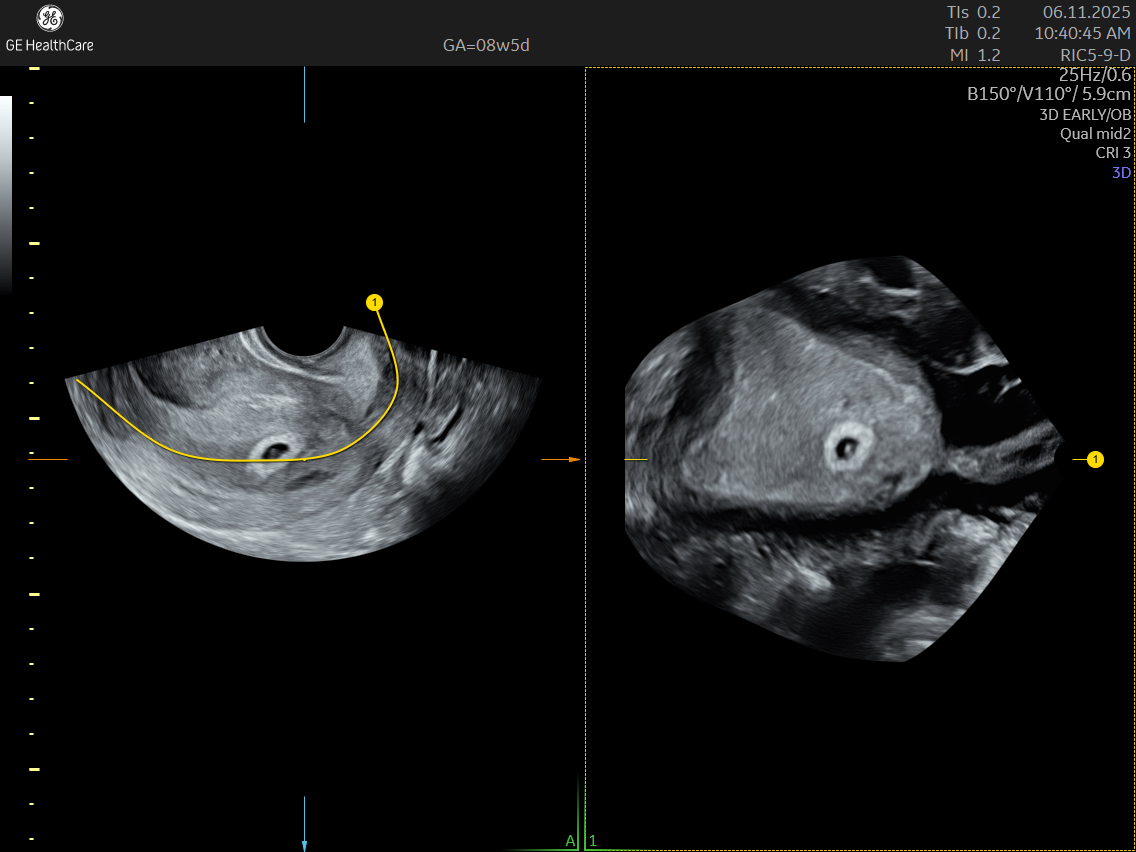

A Dating and Viability Scan is the first critical ultrasound in your pregnancy journey. Performed between 6 – 8 weeks, it confirms your pregnancy’s health, establishes how far along you are, and ensures an accurate start to your prenatal care.

- Usually conducted transvaginally for clear imaging

What Can The Scan Detect?